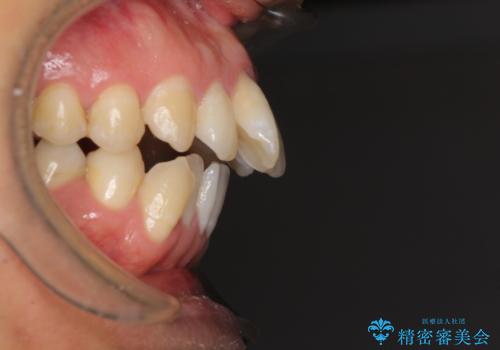

- 前歯のデコボコと、上顎前歯の突出感を気にして来院された患者様です。

通常の咬み合わせ位置と比較して、上顎の歯列が全体的に前方にある状態で、上下前歯の前後方向の位置に著しい差がありました。

上顎奥歯付近にアンカースクリューを用い、上顎歯列全体の後方移動と、大臼歯圧下を促し、前歯の上下関係を改善することとしました。